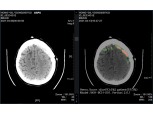

SK C&C, ‘AI 뇌출혈 영상 의료 솔루션’ 전문의 수준으로 진단

SK㈜ C&C(대표 윤풍영)가 개발한 인공지능(AI) 뇌출혈 영상 의료 솔루션 ‘메디컬 인사이트 플러스 뇌출혈(Medical Insight+ Brain Hemorrhage)’의 효과성을 입증한 논문이 국제 학술 저널에 실렸다. 3일 SK㈜ C&C에...